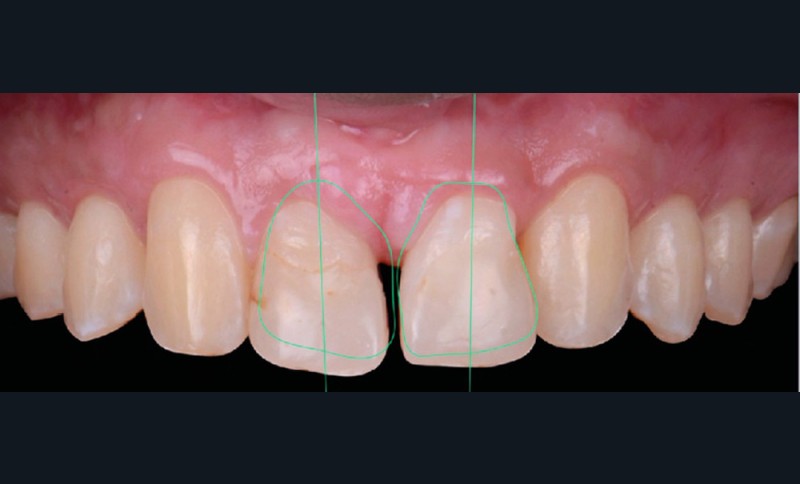

Une fois la croissance alvéolaire terminée, le patient est réadressé à son chirurgien-dentiste pour définir précisément, à l’aide d’une prévisualisation informatique (Digital Smile Design), quelle position dentaire et gingivale est recherchée pour les quatre dents antérieures (fig. 4 a,b) [4]. Le torque et le tip sont particulièrement importants à corriger dans cette phase de reprise de traitement (de quelques mois) car la position des collets et la conservation tissulaire en dépendent fortement.

Les restaurations composites transitoires réalisées au cours du premier traitement cherchant à restaurer l’esthétique de 12 et 22 masquent l’asymétrie de correction des axes radiculaires. La lecture des informations du deuxième et du troisième ordre est ainsi faussée par l’anatomie coronaire perturbée. Une individualisation par plicature est donc nécessaire pour s’approcher au mieux de la prévisualisation, avec pour seuls guides les axes radiculaires radiologiques et la position des collets souhaités (fig. 4a,b).